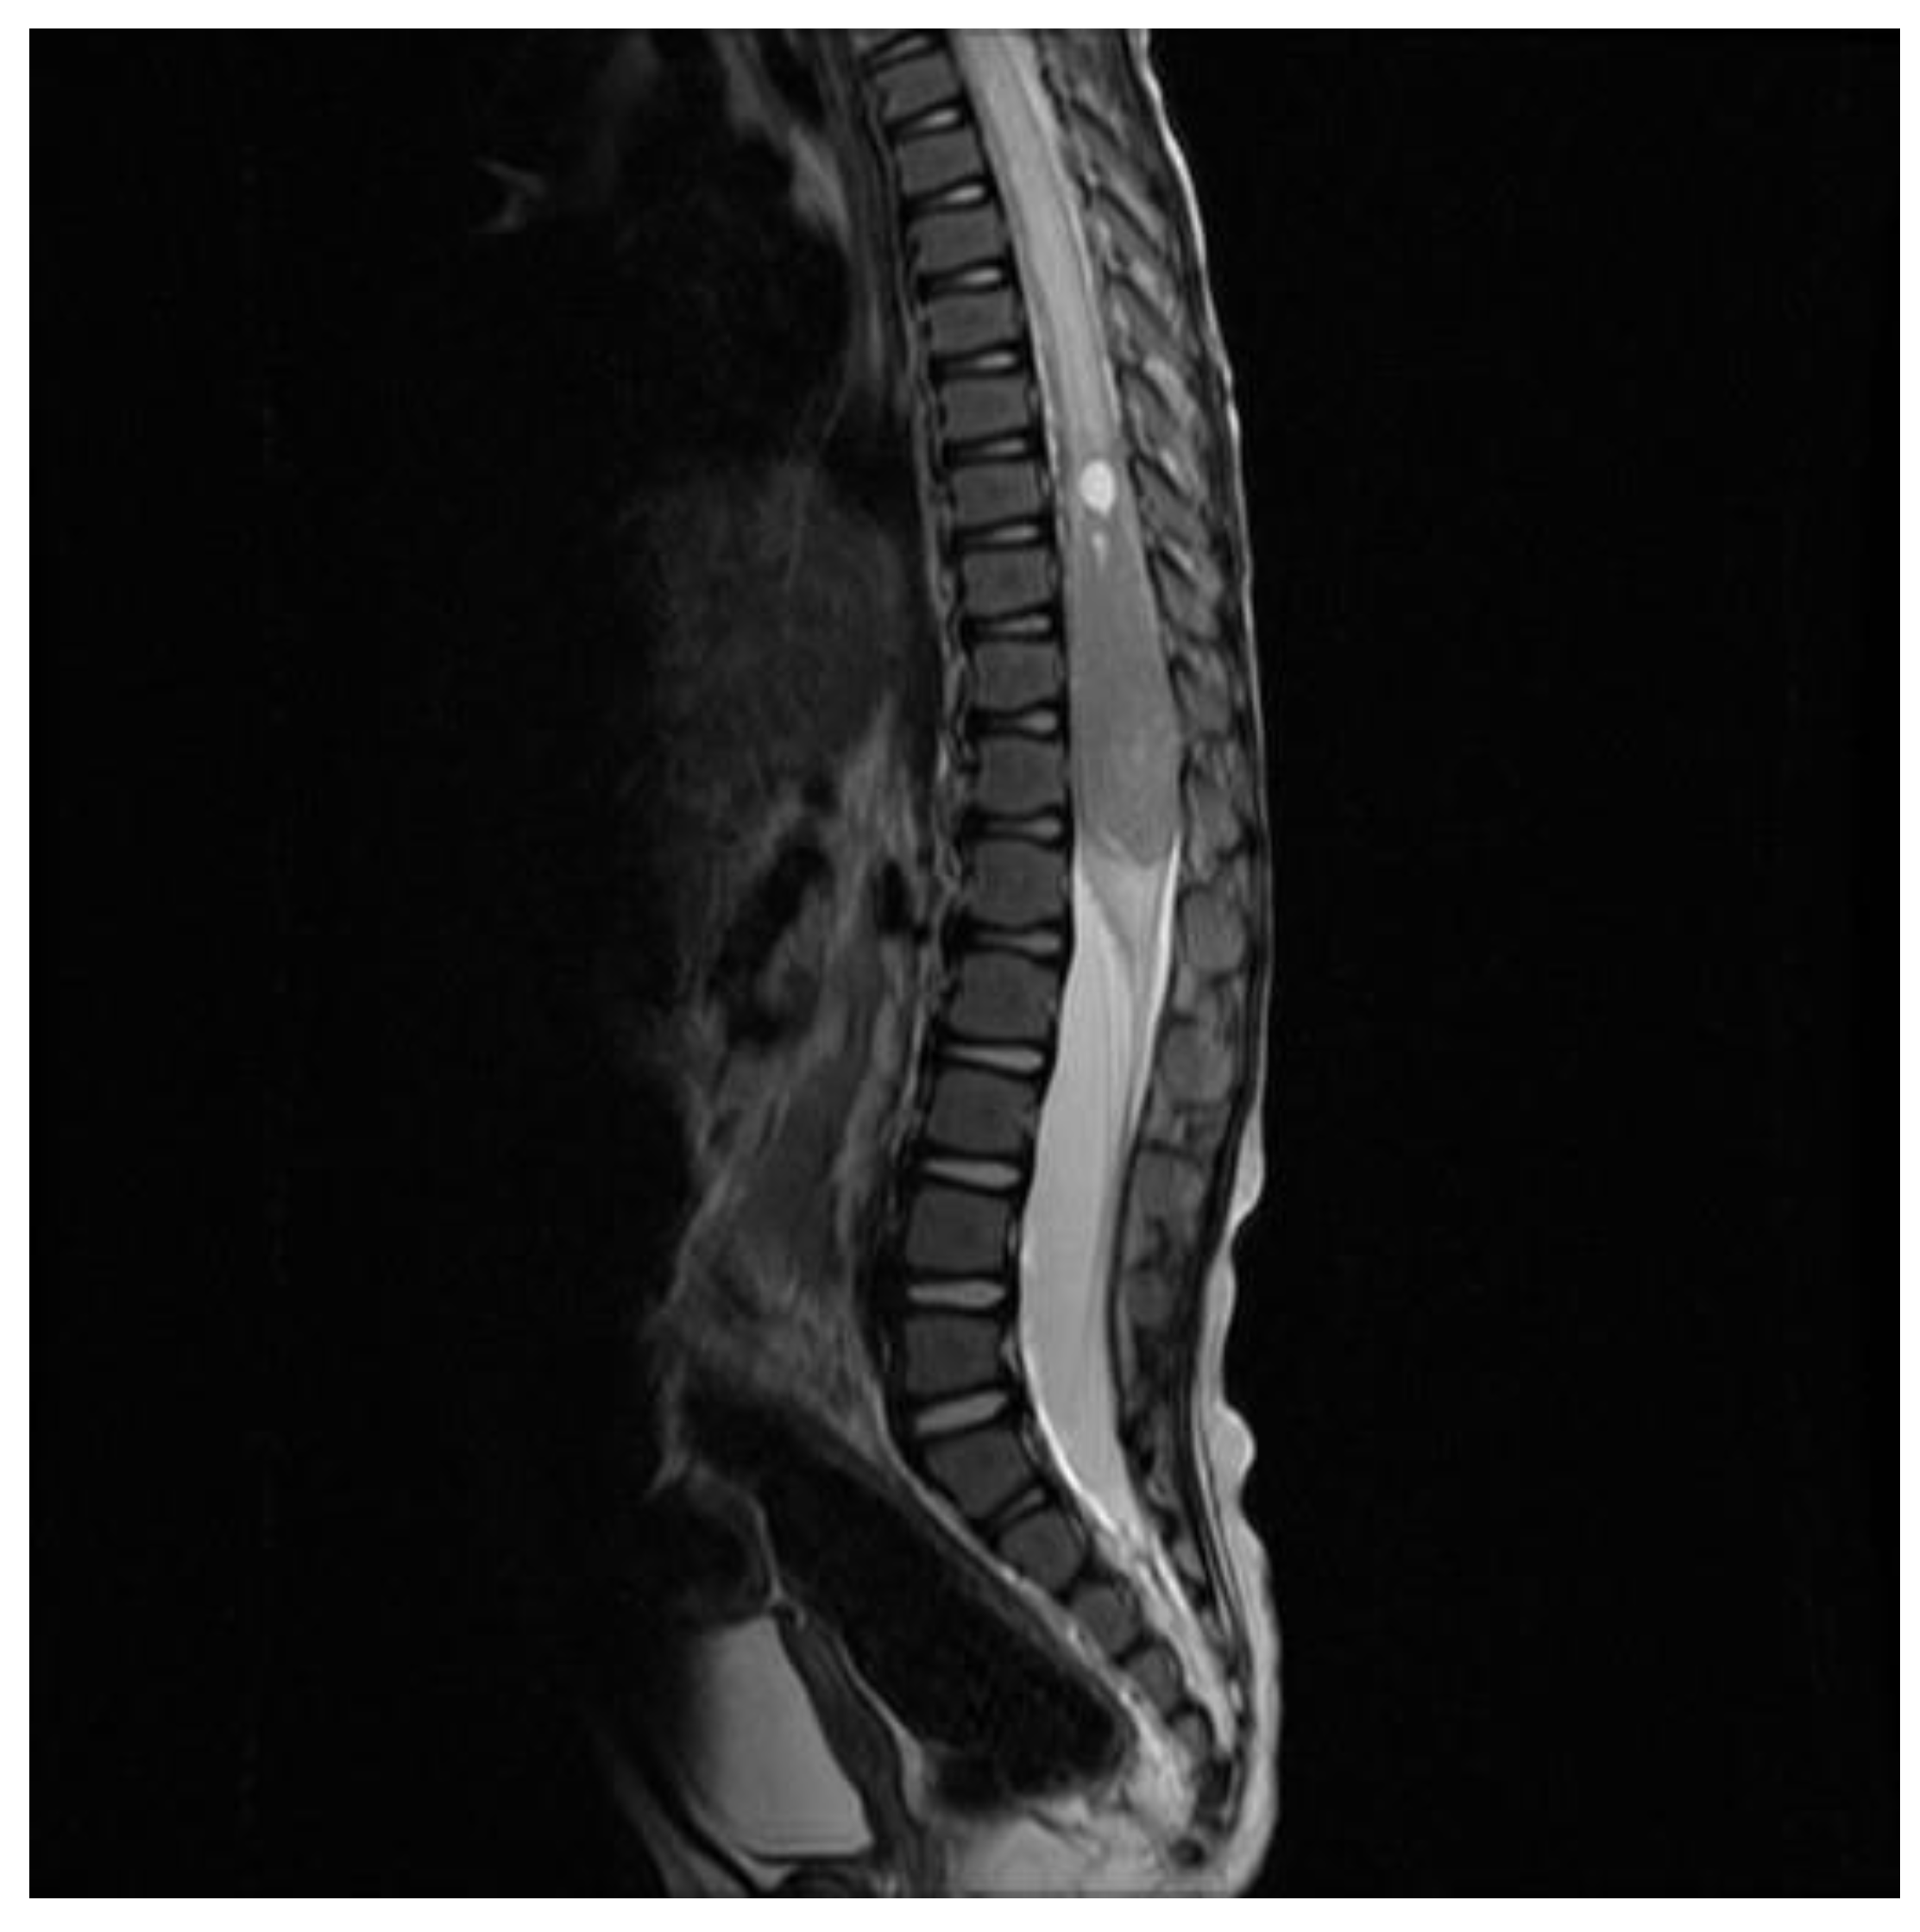

2. Case Report

5. Clinical Evolution